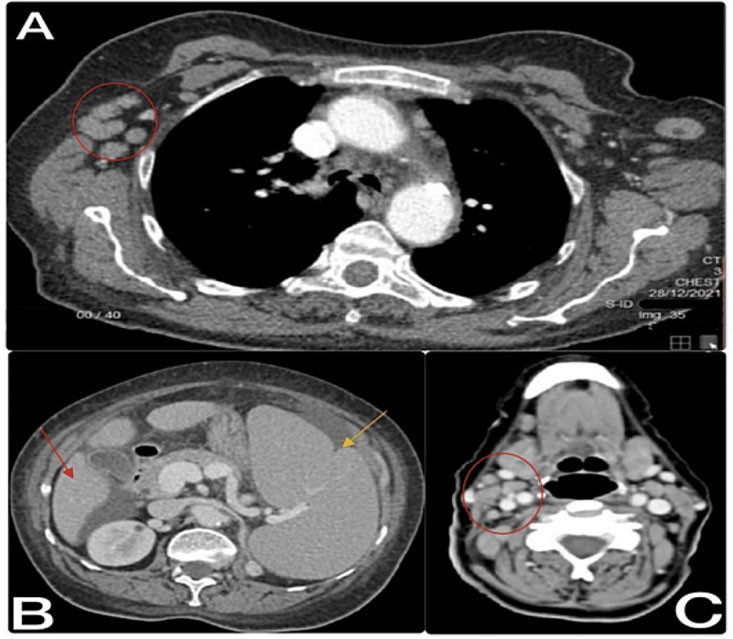

• Imaging tests: Full-body CT showed supra- and infra-diaphragmatic lymphadenopathy, hepatosplenomegaly, and a suspicious left adrenal gland lesion. CT examination of the brain showed no evidence of acute brain injury or space-occupying lesions.

Full-body CT findings: (A) CT of the chest showed multiple enlarged axillary lymph nodes (red circle). (B) CT of the abdomen showed hepatosplenomegaly with minimal ascites (red arrow - spleen, yellow arrow - liver). (C) CT of the neck showed multiple prominent upper neck lymph nodes (red circle - cervical lymph node).